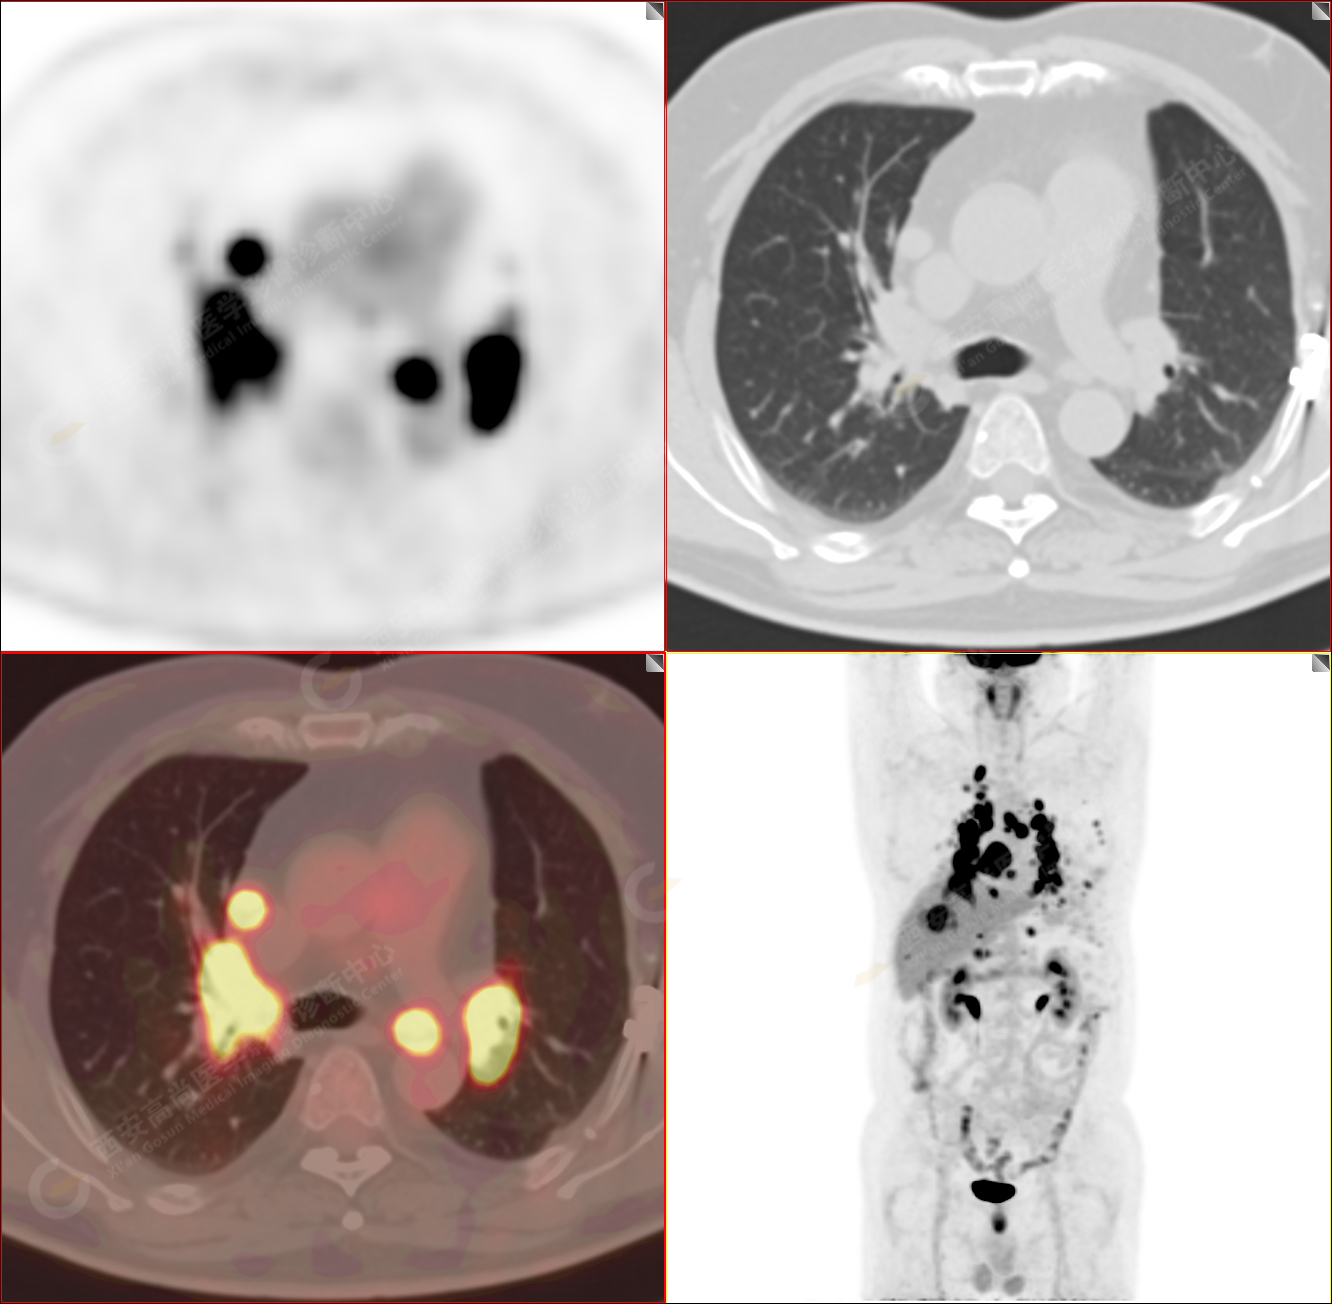

PET/CT-MR診斷結(jié)節(jié)病雙肺及全身多發(fā)淋巴結(jié)廣泛累及1例【西安高尚病例】

男性,53歲,頭暈半月入院,CT發(fā)現(xiàn)肺內(nèi)腫塊,雙肺多發(fā)大小不等實(shí)性及粟粒樣結(jié)節(jié),雙肺門(mén)及縱隔多發(fā)腫大淋巴結(jié)。病程中無(wú)發(fā)熱、胸悶氣及胸部不適。既往:左側(cè)肋骨外傷史。

PET/CT圖像